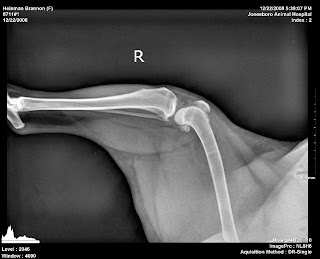

Heisman's initial set of x-rays are below - confirming no hip dysplasia (YAY) as well as no other fractures to her leg. As in humans, you cannot see the ligament tear in the x-ray. That must be diagnosed be the doctor checking for unnecessary and unnatural mobility in the knee joint, which is certainly present in Heisman.